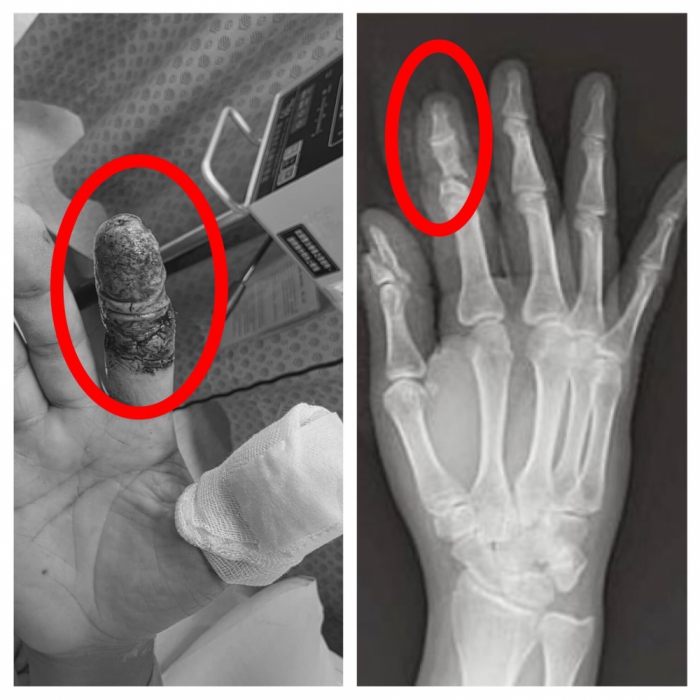

【記者林獻元台中報導】豐原一名45歲林姓男子日前操作大型無人機時發生意外,高速旋轉的螺旋槳瞬間擊中右手,食指幾乎完全斷離,僅剩少量皮膚相連,傷勢嚴重,緊急送往衛生福利部豐原醫院救治,經外科醫師陳明澤評估屬重大手指創傷,若血流未恢復恐須截指,立即進行清創與重建手術,透過顯微技術接合受損血管與組織,成功建立循環,為後續組織存活爭取關鍵時間。

豐原醫院外科醫師陳明澤指出,手指血管直徑僅約1-2毫米,顯微重接只是第一步,真正挑戰在於術後微血管血流的關鍵觀察期。陳醫師進一步表示,再接手指的血流極度脆弱,任何血栓都可能讓前功盡棄,因此團隊術後並未僅止於觀察,而是每日主動進行局部抗凝處置的特殊浸泡照護,使用的「Heparin」抗凝血藥物,採局部浸泡,輔助維持血管暢通、減少血栓形成風險,此療法屬於較細緻的術後血流管理策略,醫護人員需密集監測顏色、溫度與出血反應,是術後照護能力的重要延伸。

陳明澤提到,患者住院期間長達一個月,初期因傷勢嚴重、復原緩慢,一度情緒低落甚至萌生放棄治療與轉院念頭,但在醫療團隊持續關懷與專業照護下逐步配合治療,隨著每日血流管理、一個月的高壓氧積極治療,手指循環逐步穩定、組織存活情況日益改善,讓患者逐漸重拾信心,最終順利出院,成功保住手指外觀與功能。